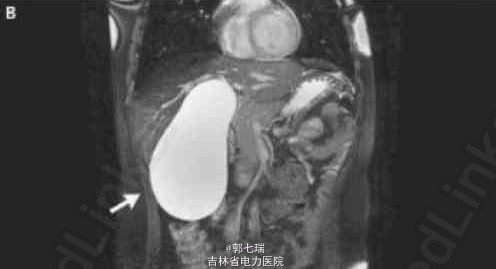

实验室检查(包括肝酶的检测)结果没有值得注意之处。 腹部超声检查所见异常,此后的腹部磁共振成像显示胆囊明显扩张(图A,轴位影像,箭;图B,冠状面重建影像,箭),测量值为17 cm×8 cm,但没有胆结石、胆管树的外源性压迫或胆管扩张的证据。

临床诊断为:胆囊积水。行腹腔镜下胆囊切除术,并且术中从胆囊抽出的无色黏液。 该病人的症状在手术后消失,并且她在1年后随访时仍无症状。